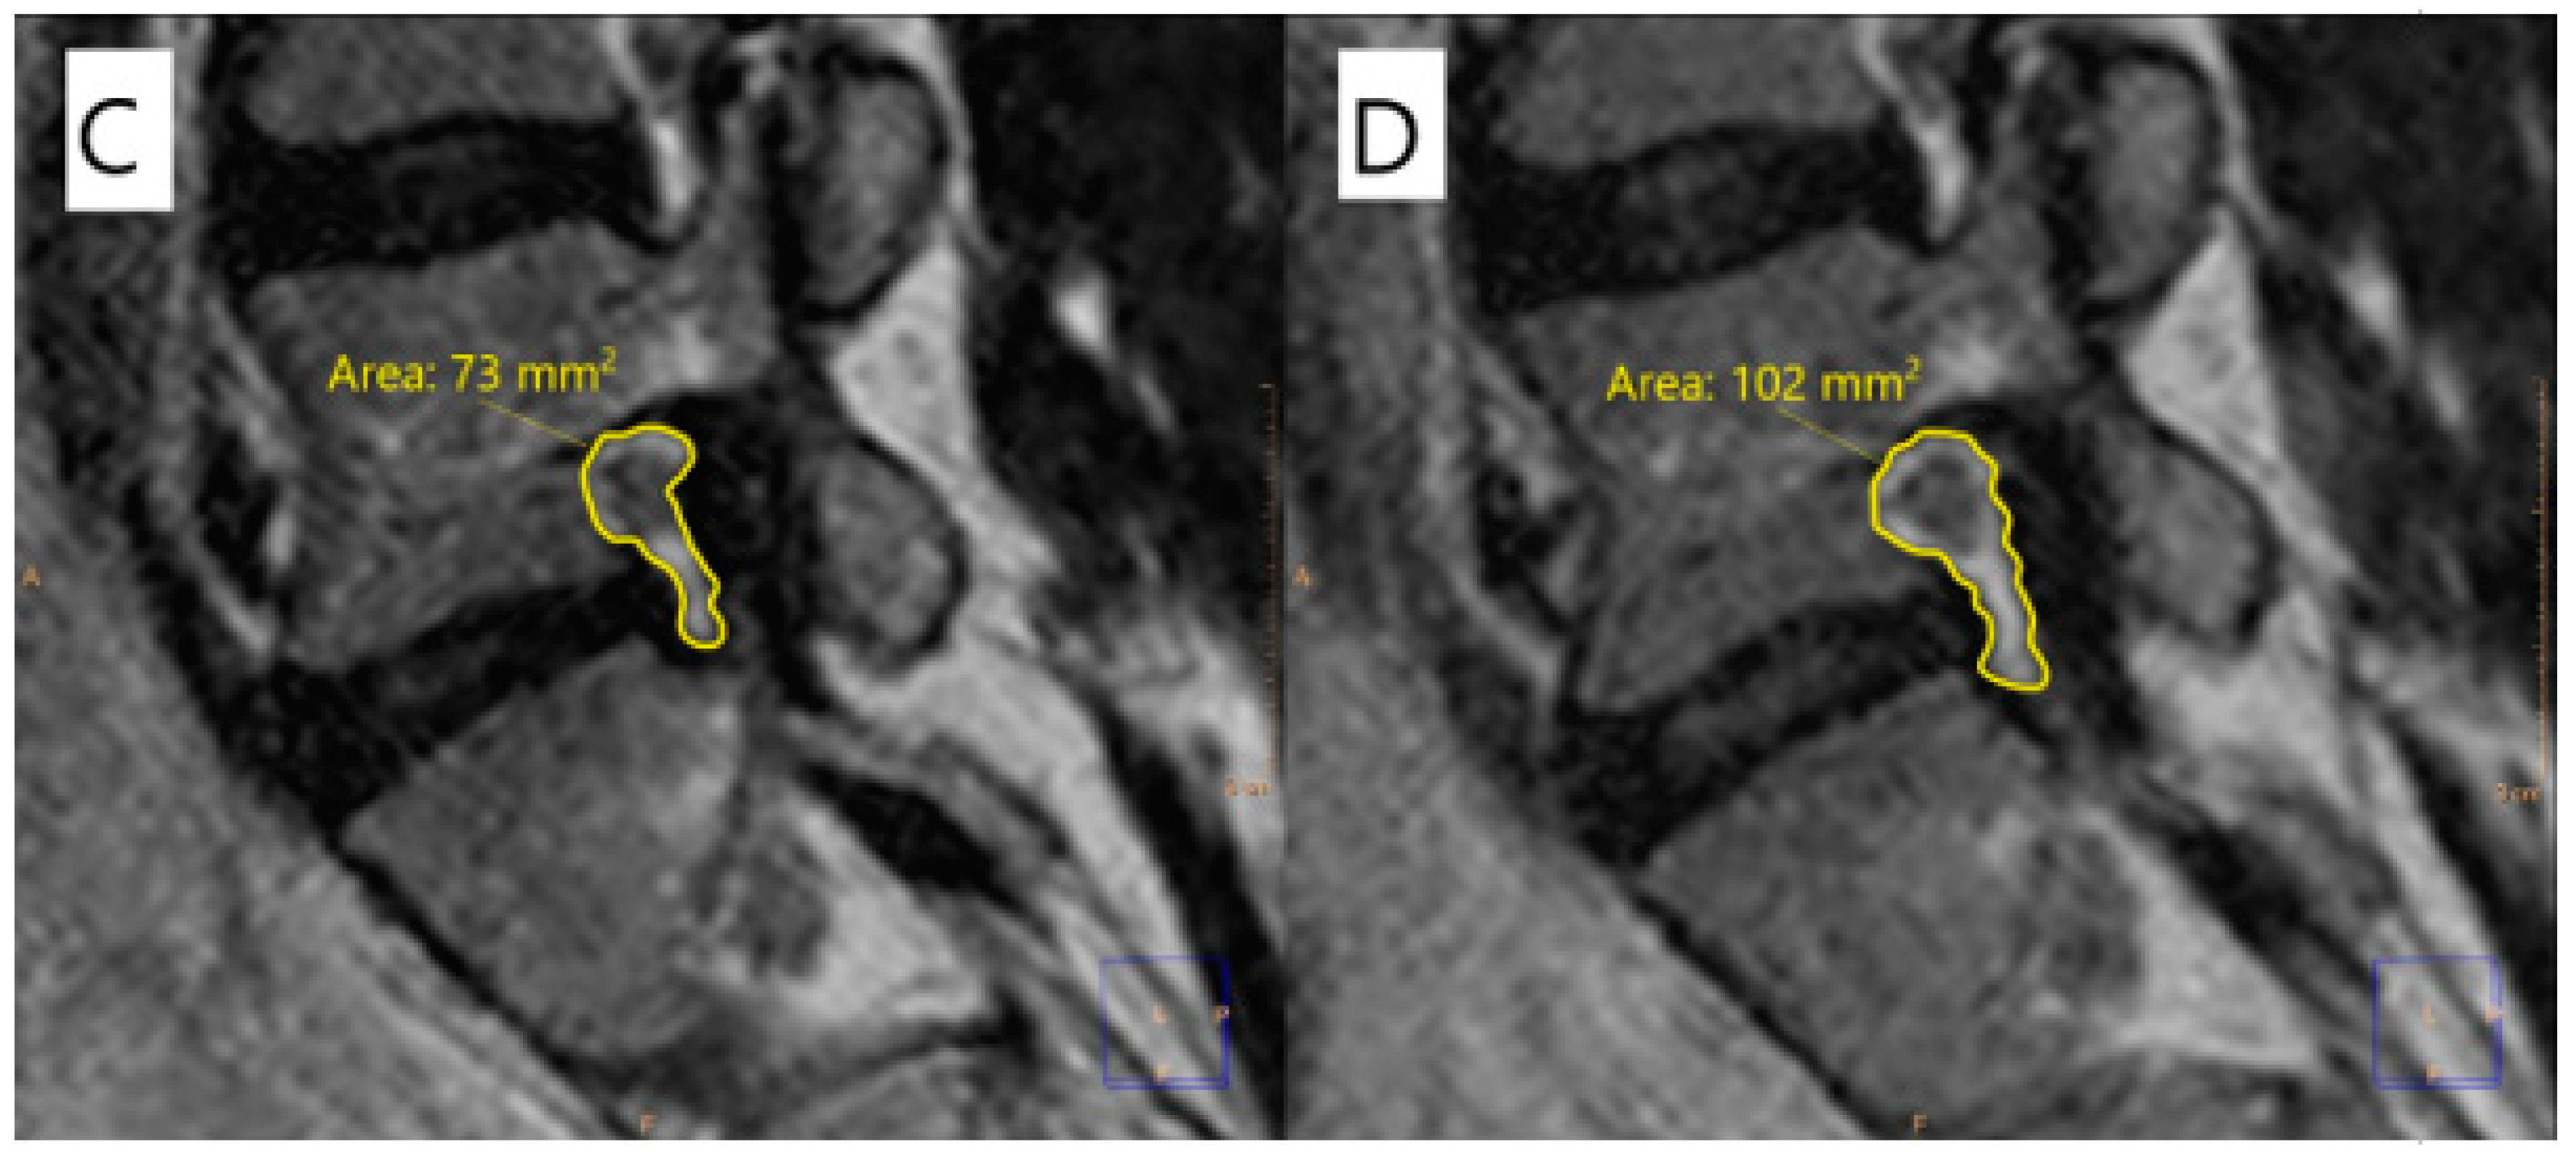

2.2. Image Analysis